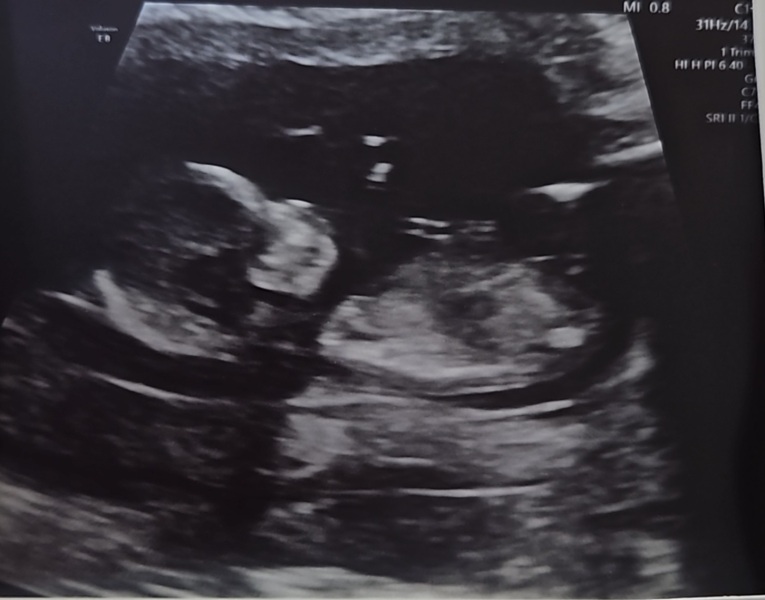

Can someone guess with me the gender for fun the with nub theory on my scan.

I'm not sure either as it's faint at one end of the scan the baby didn't want to stay still so this was the best we got at 13 weeks

Kate0000000000 · 10/10/2023 17:06

Girl